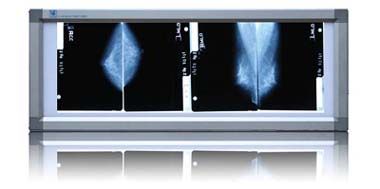

乳腺觀片燈

乳腺觀片燈

乳腺觀片燈